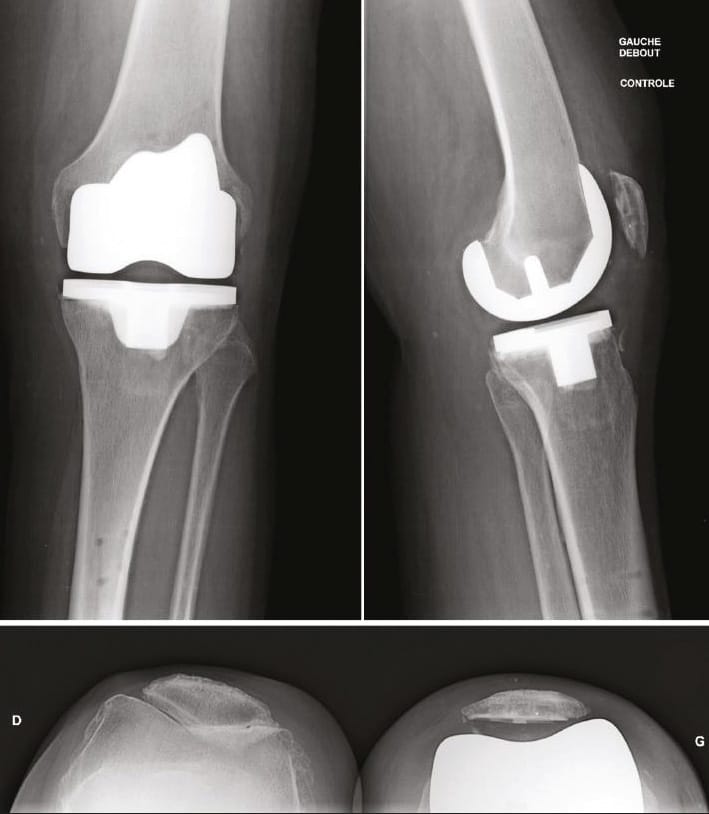

During the transition period, when appointments for patients undergoing surgery 3 months previously via the medial route coincided with those for patients undergoing surgery 1 month earlier via the lateral subvastus route (Figures 11 & 12), we realized that convalescence had been reduced by 2 months. A multi-centre study comparing the two types of approach is currently under way.

The functional scores are identical but the side on which the lateral, minimally invasive route was used is more comfortable. Radiographic assessment demonstrates that patellar alignment is always perfect with the lateral subvastus route.